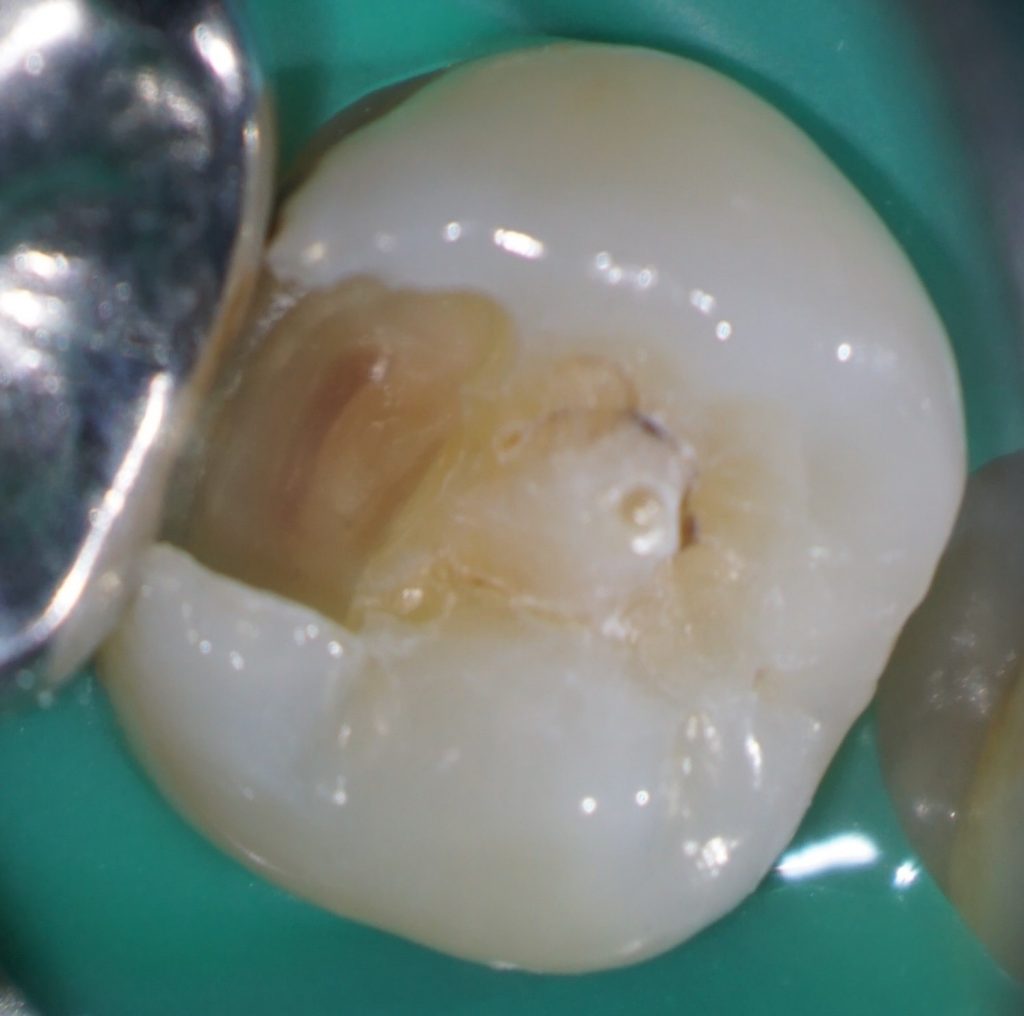

たとえば、この症例はいかがでしょう。

中心結節がある症例では、中心結節に歯髄が嵌入していることが知られています。

この症例を普通に治そうとするとインレーになりますよね。

しかし、通法の形成ではイスムスを形成しているときに露髄してしまうかもしれません。

私はこういった症例の治療をする場合、う蝕を取り除き、

露髄していないことを確認したうえで、コンポジットレジンで修復することがほとんどです。

これを自由診療で行っています。

患者さんは、歯髄を失わなくて済むので自由診療を選択したことをとても喜んでくれます。

少し高額な治療でも、「歯髄を残したい」という患者さんはとても多いと思います。